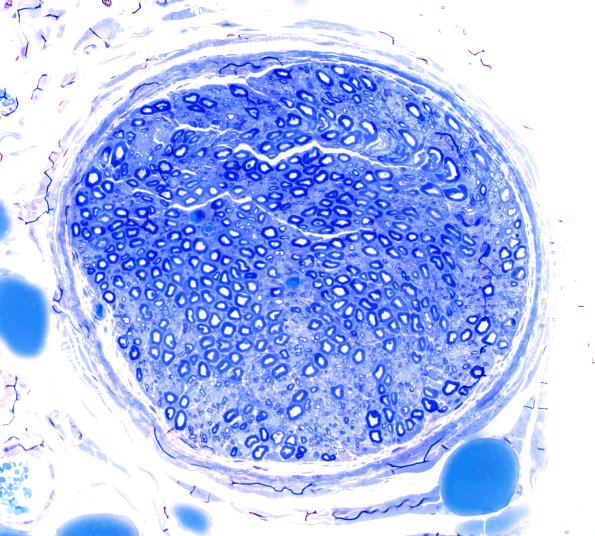

Case 6 History ---- The patient is a 57-year-old woman with diabetic polyneuropathy associated with type 2 diabetes mellitus. Operative procedure: Left lateral antebrachial cutaneous nerve (LABC) biopsy. ---- 6A1,2 We have even less experience with this sensory nerve. The plastic sections show a prominence of large myelinated axons and would be quite abnormal for a sural nerve population. (Toluidine-blue stained one-micron thick plastic embedded section)